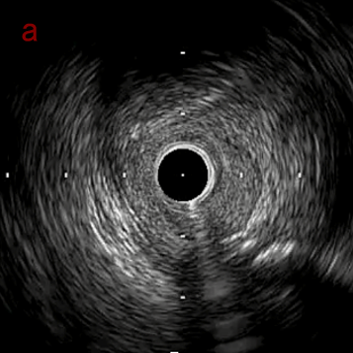

IVUS after OAS high speed 3回

IVUS imaging after high speed 3回

a,b,cはさらに石灰化に食い込み、石灰化量は減少。

それに伴いdではbiasがさらにtentingのIVUS所見にへんかしhigh injury riskと思われた。

引き続き造影で確認してpinpointで引きのOAS high speedを3回さらに追加のためcでIVUSマーキングを行い、その点より引きで赤線のpinpoint OAS high speedを行い、dに関してはinjury回避のためにOASを当てない方針とした。